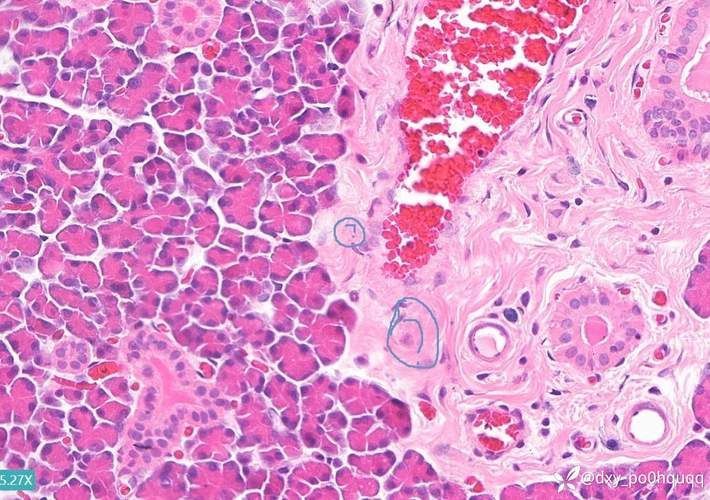

顯微鏡下特征(關鍵鑒別點):

- 指環蟲:蟲體呈蠕蟲狀,長約0.5–2mm,具兩個錨狀附著器,可見顎片;

- 鰓隱鞭蟲:柳葉形,前端具兩根不等長鞭毛,后鞭毛與波動膜相連,運動迅捷;

- 小瓜蟲:鰓絲上可見白色點狀胞囊(直徑0.2–0.5mm),蟲體成熟后破裂釋放幼蟲。

三、確診金標準:鰓絲鏡檢操作流程

- 制片觀察:將刮取物置于載玻片,加1滴清水,蓋上蓋玻片;

- 顯微鏡檢查:使用40–400倍光學顯微鏡,先低倍(10×)定位,再高倍(40×)觀察蟲體形態。